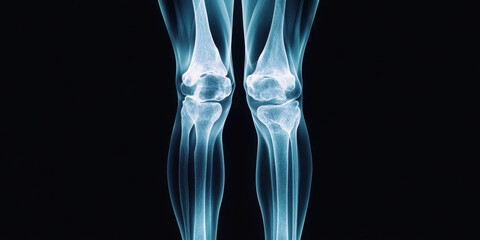

Podobny obraz Medical Elbow Anterior View X-Ray Radiograph Illustrating...